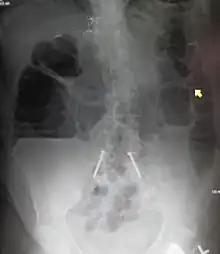

Radiological signs of bowel obstruction include bowel distension and the presence of multiple (more than six) gas-fluid levels on supine and erect abdominal radiographs. Ultrasounds may be as useful as CT scanning to make the diagnosis.[13]

Contrast enema or small bowel series or CT scan can be used to define the level of obstruction, whether the obstruction is partial or complete, and to help define the cause of the obstruction. The appearance of water-soluble contrast in the cecum on an abdominal radiograph within 24 hours of it being given by mouth predicts resolution of an adhesive small bowel obstruction with sensitivity of 97% and specificity of 96%.[14]

Some causes of bowel obstruction may resolve spontaneously;[16] many require operative treatment.[17] In adults, frequently the surgical intervention and the treatment of the causative lesion are required. In malignant large bowel obstruction, endoscopically placed self-expanding metal stents may be used to temporarily relieve the obstruction as a bridge to surgery,[18] or as palliation.[19] Diagnosis of the type of bowel obstruction is normally conducted through initial plain radiograph of the abdomen, luminal contrast studies, computed tomography scan, or ultrasonography prior to determining the best type of treatment.[20]